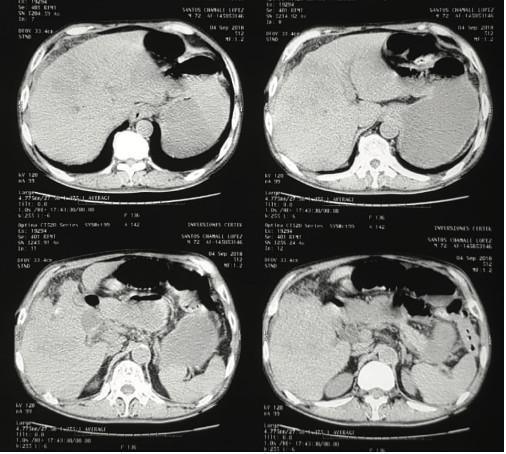

Laboratorios de ingreso con leucocitosis (13,500) y for- mula diferencial con neutrofilia (92%), química sanguínea sin alteración hidroelectrolítica, con bilirrubinas totales en 2.1 directa en 1.6 indirecta en 0.5, GGT en 560. A las 6 horas de ingreso distensión mejora y logra defecar por lo que continua en observación. A las 12 horas del ingreso paciente vuelve a distenderse y presentar vómitos por lo que se realiza tac abdominal (Figuras 2 y 3).

Figura 2. Tomografía abdominal que demuestra a nivel hepático neumo- bilia, además no se logra diferenciar adecuadamente lecho vesicular ni vía biliar, únicamente imágenes de infiltración a nivel de lecho hepático.